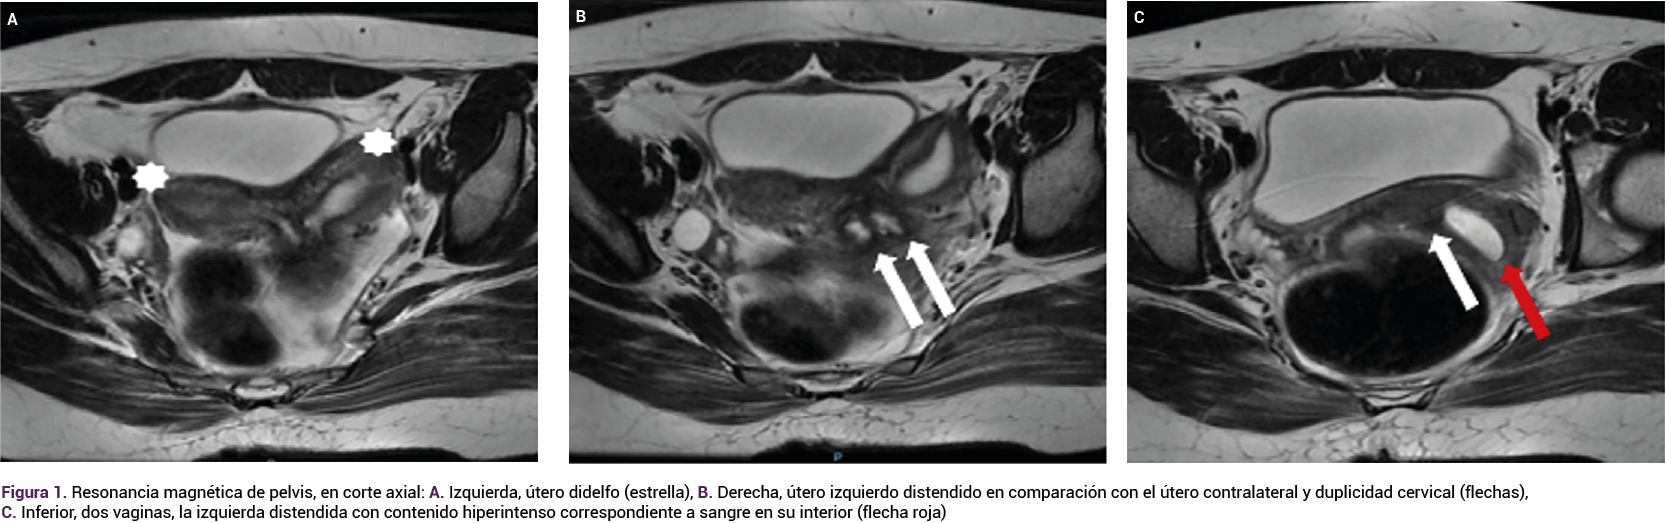

En el transcurso del control prenatal la paciente refirió flujo vaginal; en el tacto se palpó, en el fondo de saco lateral izquierdo, aumento de volumen, con presión y drenaje espontáneo de aproximadamente 20 mL de líquido fétido, verdoso. En la especuloscopia se corroboró que la secreción provenía de una aparente comunicación con la vagina izquierda, previamente obstruida. Se hospitalizó para la administración del tratamiento con antibiótico y practicar estudios de extensión. Figura 3

Figura 3.

Durante la hospitalización no se registraron alteraciones en los estudios de laboratorio de fase aguda que indicaran un proceso infeccioso sistémico; sin embargo, por las características de la secreción, se indicó un esquema antibiótico doble de amplio espectro, con adecuada evolución clínica que ameritó el alta del hospital. El control prenatal continuó en la consulta externa de obstetricia, donde se solicitó otra resonancia magnética de control para valoración de la colección derecha; el estudio reportó la ausencia de colección aparente en la vagina izquierda. Figura 4